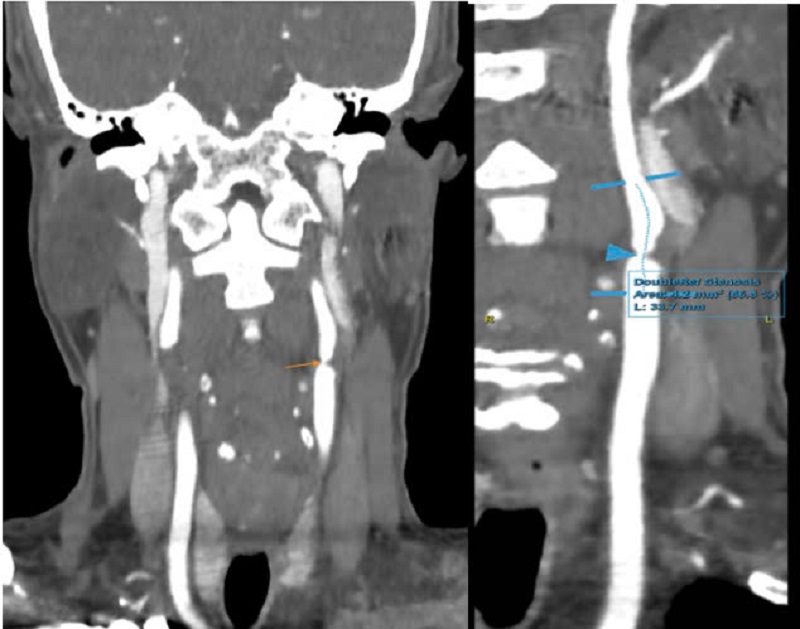

Kết quả chụp MSCT mạch cảnh của bệnh nhân cho hình ảnh mảng xơ vữa mềm gây hẹp 86% đoạn gốc động mạch cảnh trong trái, 70% vị trí hành cảnh trái, 50% vị trí hành cảnh phải và 50% đoạn gốc động mạch cảnh trong phải.

Bệnh nhân sau đó được chỉ định chụp MSCT mạch cảnh thì cho hình ảnh mảng xơ vữa mềm gây hẹp 86% đoạn gốc động mạch cảnh trong trái, 70% vị trí hành cảnh trái, 50% vị trí hành cảnh phải và 50% đoạn gốc động mạch cảnh trong phải.

Do vậy, bác sĩ chẩn đoán xác định bệnh nhân mắc bệnh động mạch cảnh do vữa xơ không triệu chứng gây hẹp đáng kể động mạch cảnh hai bên/ tăng huyết áp. Sau đó, bệnh nhân được kê đơn điều trị bệnh để tránh biến chứng.